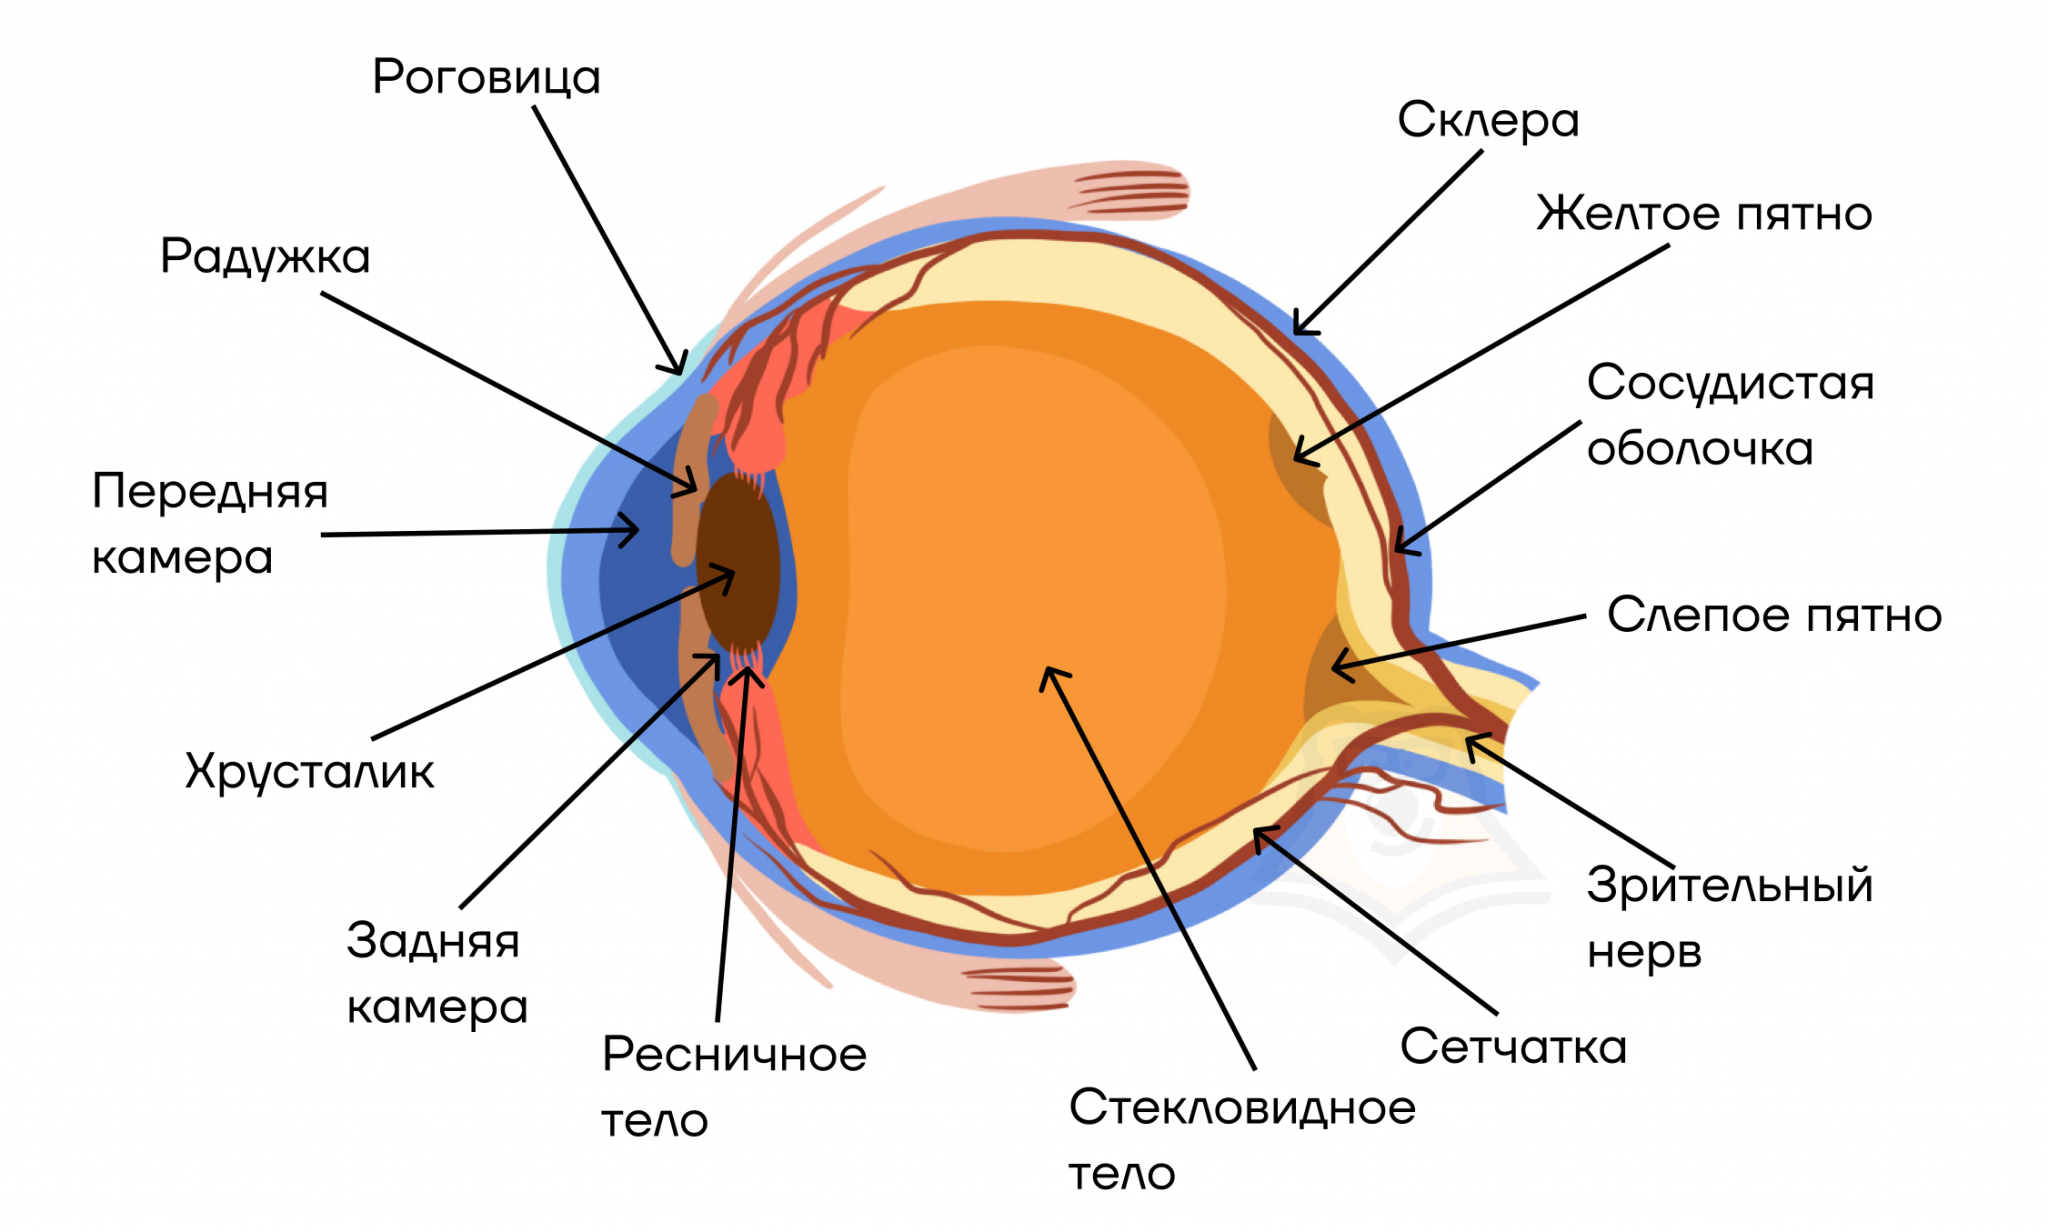

КТ-графики и изображение строения глаза